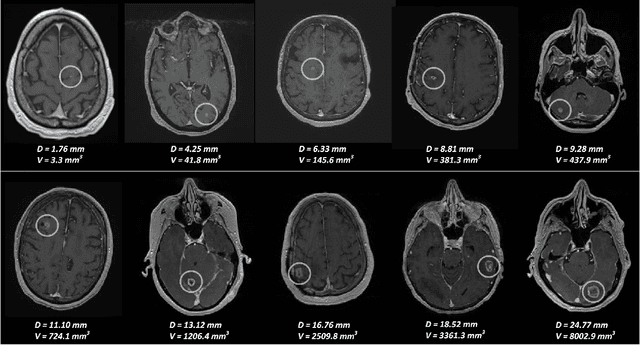

Abstract:The detection of brain metastases (BM) in their early stages could have a positive impact on the outcome of cancer patients. We previously developed a framework for detecting small BM (with diameters of less than 15mm) in T1-weighted Contrast-Enhanced 3D Magnetic Resonance images (T1c) to assist medical experts in this time-sensitive and high-stakes task. The framework utilizes a dedicated convolutional neural network (CNN) trained using labeled T1c data, where the ground truth BM segmentations were provided by a radiologist. This study aims to advance the framework with a noisy student-based self-training strategy to make use of a large corpus of unlabeled T1c data (i.e., data without BM segmentations or detections). Accordingly, the work (1) describes the student and teacher CNN architectures, (2) presents data and model noising mechanisms, and (3) introduces a novel pseudo-labeling strategy factoring in the learned BM detection sensitivity of the framework. Finally, it describes a semi-supervised learning strategy utilizing these components. We performed the validation using 217 labeled and 1247 unlabeled T1c exams via 2-fold cross-validation. The framework utilizing only the labeled exams produced 9.23 false positives for 90% BM detection sensitivity; whereas, the framework using the introduced learning strategy led to ~9% reduction in false detections (i.e., 8.44) for the same sensitivity level. Furthermore, while experiments utilizing 75% and 50% of the labeled datasets resulted in algorithm performance degradation (12.19 and 13.89 false positives respectively), the impact was less pronounced with the noisy student-based training strategy (10.79 and 12.37 false positives respectively).

Abstract:Early detection of brain metastases (BM) is one of the determining factors for the successful treatment of patients with cancer; however, the accurate detection of small BM lesions (< 15mm) remains a challenging task. We previously described a framework for the detection of small BM in single-sequence gadolinium-enhanced T1-weighted 3D MRI datasets. It combined classical image processing (IP) with a dedicated convolutional neural network, taking approximately 30 seconds to process each dataset due to computation-intensive IP stages. To overcome the speed limitation, this study aims to reformulate the framework via an augmented pair of CNNs (eliminating the IP) to reduce the processing times while preserving the BM detection performance. Our previous implementation of the BM detection algorithm utilized Laplacian of Gaussians (LoG) for the candidate selection portion of the solution. In this study, we introduce a novel BM candidate detection CNN (cdCNN) to replace this classical IP stage. The network is formulated to have (1) a similar receptive field as the LoG method, and (2) a bias for the detection of BM lesion loci. The proposed CNN is later augmented with a classification CNN to perform the BM detection task. The cdCNN achieved 97.4% BM detection sensitivity when producing 60K candidates per 3D MRI dataset, while the LoG achieved 96.5% detection sensitivity with 73K candidates. The augmented BM detection framework generated on average 9.20 false-positive BM detections per patient for 90% sensitivity, which is comparable with our previous results. However, it processes each 3D data in 1.9 seconds, presenting a 93.5% reduction in the computation time.